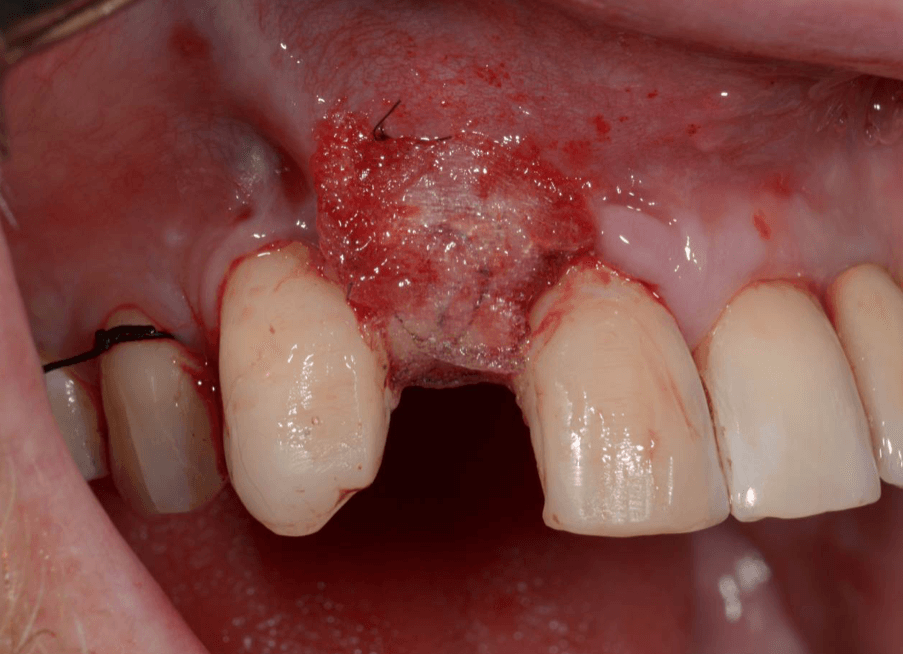

Während oder nach oralen Operationen, von der Extraktion von Zähnen bis hin zu rekonstruktiven Eingriffen, oder Implantationen, bietet BloodSTOP® iX eine schnelle und vorübergehende Kontrolle von Oberflächenblutungen.

BloodSTOP® iX absorbiert schnell Blut und verwandelt sich in ein klares Gel, um die Wunde mit einer transparenten Schutzschicht zu versiegeln, Blutplättchen zu binden und zu aktivieren, sowie die Gerinnung und Wundheilung zu unterstützen.

Anwendungsbeispiele

- Wundversorgung nach Entnahme von Weichgewebstransplantaten